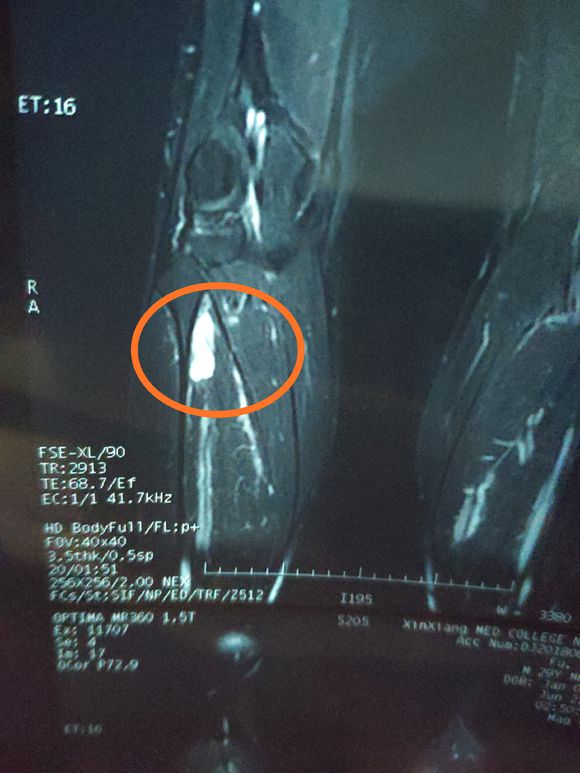

一路向北 02019-01-28 患者家属我孩子今年15岁,年初查出骨肉瘤,左腿关节处,化疗5次做载肢,手术后伤口感染误了化疗,两个多月快三个月发生肺转,如今刚住...